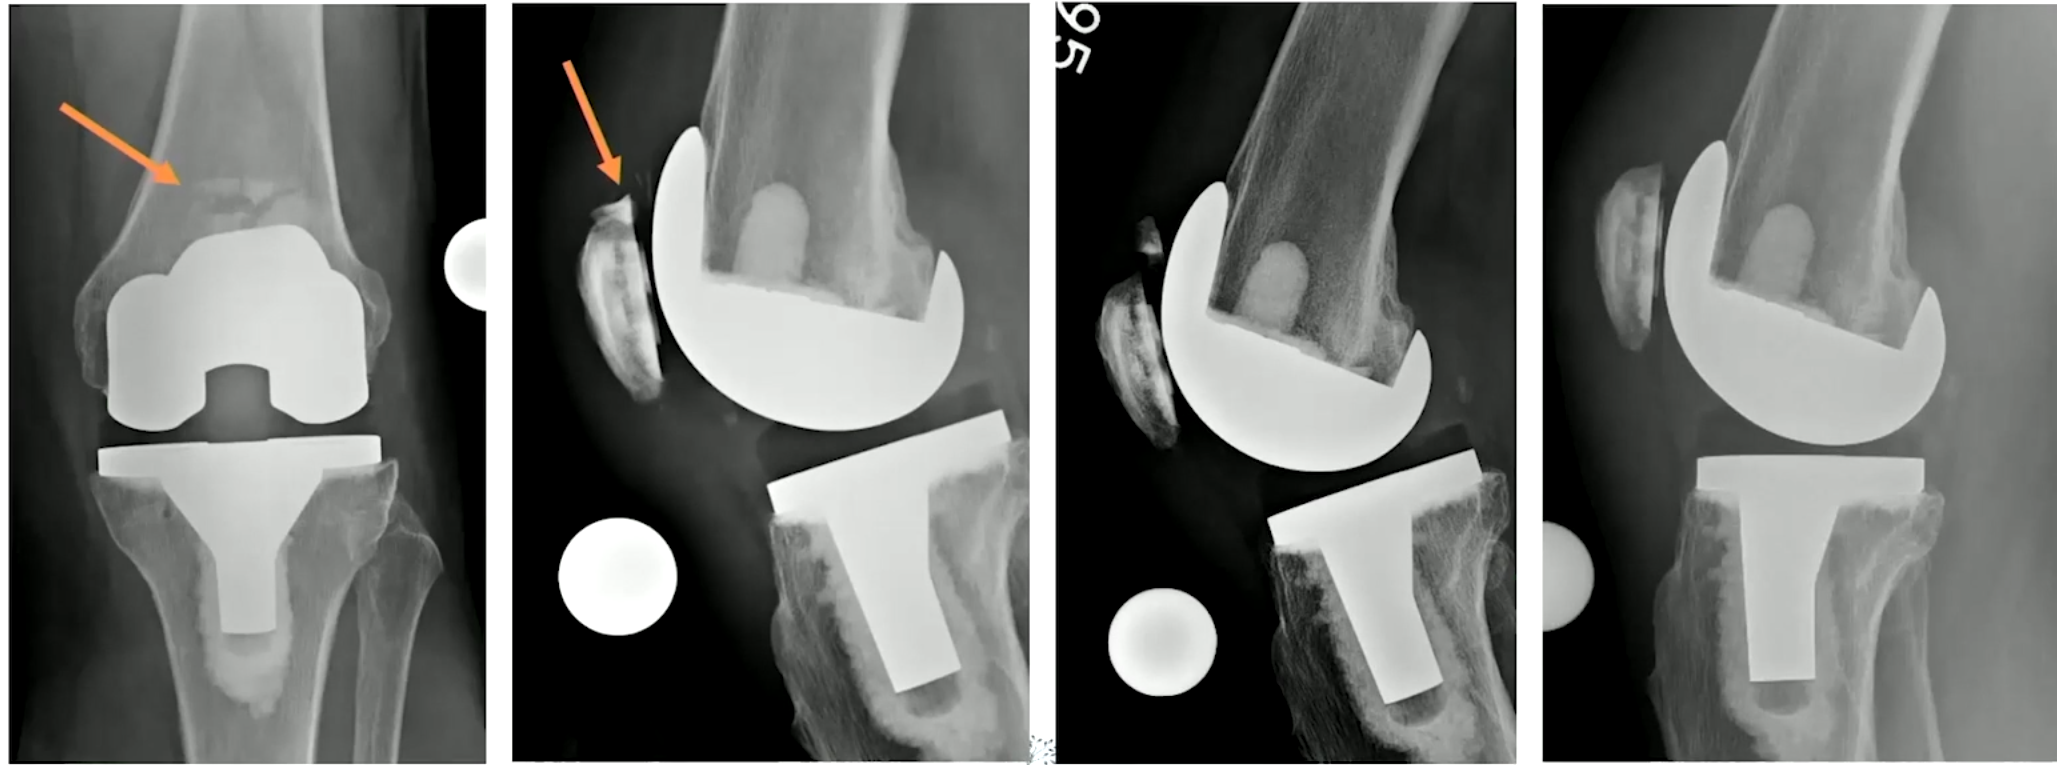

Type I, II, III 로 나뉠 수 있는데 모두 intact한 경우 I, implant는 intact하나 extensor mechanism이 작동하지 않을 때는 II, implant도 loosening 되고, implant 도 풀린 경우에는 III 로 나뉠 수 있습니다.

중요한 것은 Type II 인데, 폄근의 기능을 상실하였기 때문에 수술적인 치료가 필요합니다. 안에 들어간 implant는 정상일 수도 있으며, Bone Stock 이 남아있는 정도를 확인하여 수술의 종류를 설정할 수 있습니다. (대게 고령에 뼈 상태가 좋을 수 없으니 Partial patellectomy를 가장 많이 할 것 같습니다.)

아래와 같은 방식으로 여러가지 수술을 시행해 볼 수 있습니다. (ORIF, 뼈와 근육을 연결한 부위를 채취하여 기존의 patella 부분과 tibia 부분을 연결하도록 꼬매서 폄근육을 재건하는 경우, Suture anchor를 이용해서 repair 하는 경우, K-wire를 이용한 tension band wiring을 시행해 볼 수 있습니다.)

심하게 골절이 있는 경우는 슬개골을 재거하는 것 까지 생각해야 합니다.